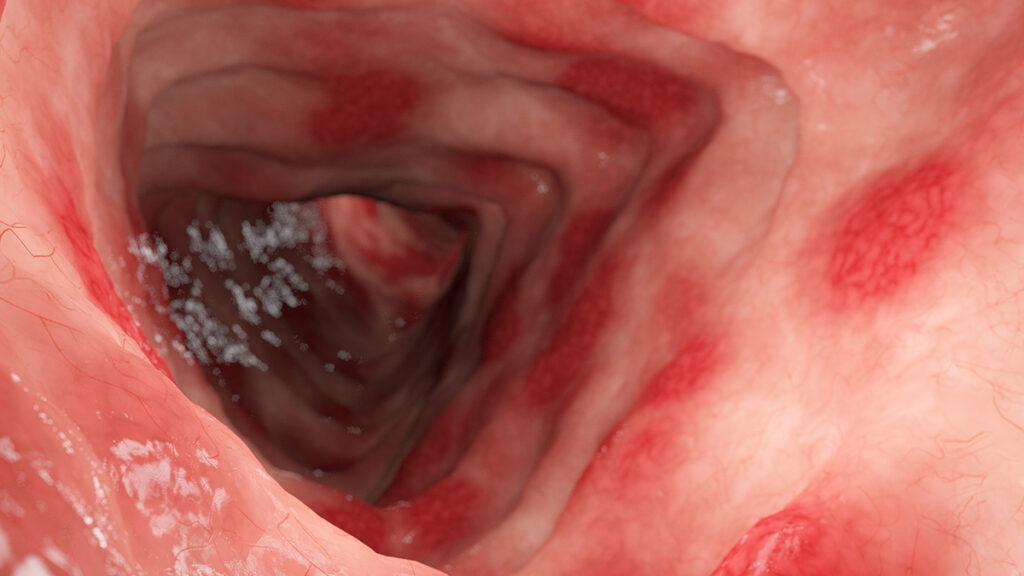

3.25 消化管障害における栄養療法の戦略 —— 消化性潰瘍、炎症性腸疾患、過敏性腸症候群への対応と再発予防

⑴消化器疾患と栄養の相互作用胃や腸の疾患、特に消化性潰瘍(胃潰瘍・十二指腸潰瘍)、潰瘍性大腸炎(UC)※下記画像、クローン病(CD)、過敏性腸症候群(IBS)などの消化管障害では、炎症やバリア機能…